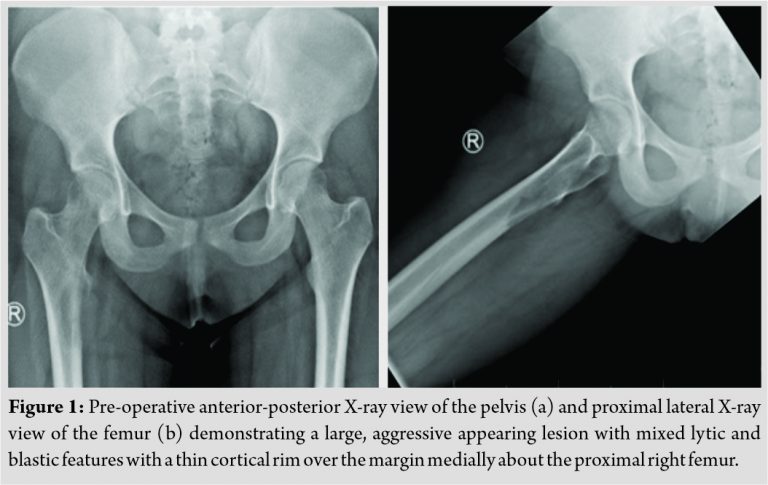

Radiographs were obtained by her primary care provider, which demonstrated a large, aggressive lesion with some mixed lytic and blastic features about the proximal femur (Fig. 1). On careful examination, there appeared to be a thin cortical rim over the margin of the lesion medially. Magnetic resonance imaging was obtained and demonstrated an aggressive appearing lesion centered near the inferomedial femoral neck as well as the lesser trochanter (Fig. 2). The lesion demonstrated a lytic appearance with some extension through the cortex. A soft tissue mass of approximately 6cm in size was present which abutted the iliopsoas and vastus musculature causing adjacent mass effect.